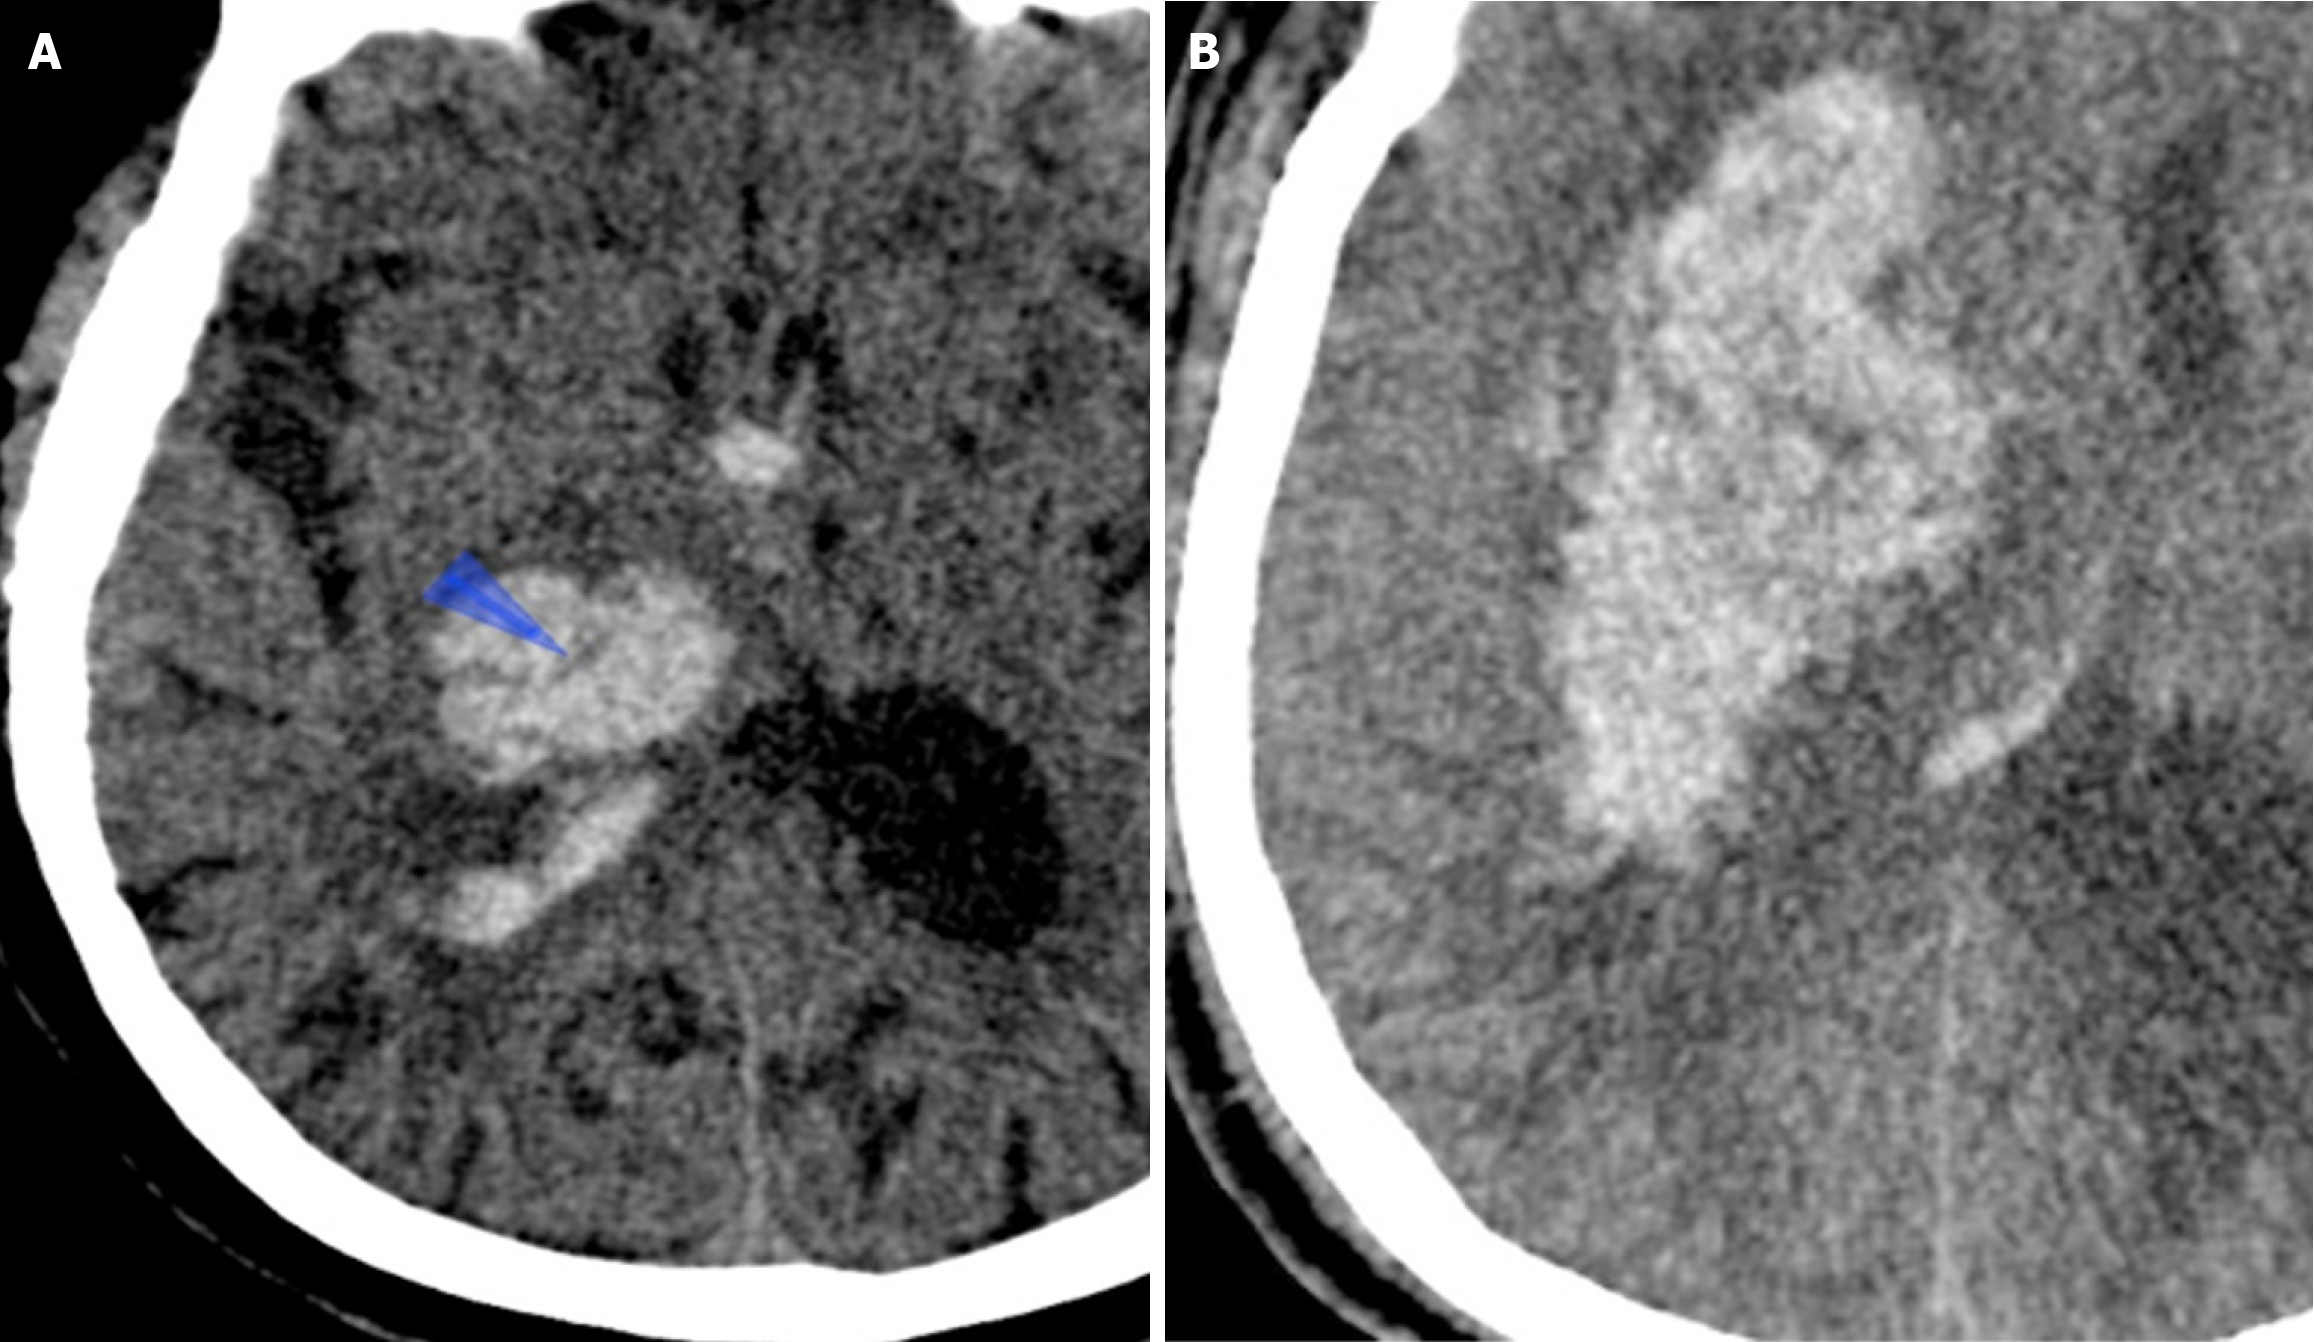

The swirl sign was defined as single or multiple areas of isoattenuation or hypoattenuation within a hyperattenuated intraparenchymal hematoma, in comparison to brain parenchyma. The shape of these regions of isoattenuation or hypoattenuation may be irregular, round, oval, or streak-like[17-19] (Figure 3).